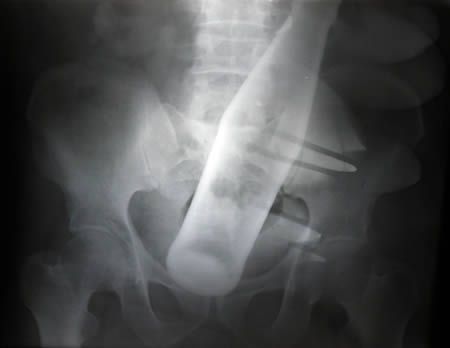

瓶は変態系統のお遊びの結果だろうな

ボトルとか瓶とかよくお尻に入れられたな

直腸内で破砕せざるを得なかった巨大直腸異物の1例

↑こんな感じで学会で報告されるそうだな…

そのままググれば文章出てくるわ

尻に異物が入る時はだいたい「転んだ拍子に」って言うけど医療関係者はそんな与太話は誰も信じてないだろうね。

おまえらケツに物入れてみたことないから笑えるんやで。後ろはホンマ気持ちええんや